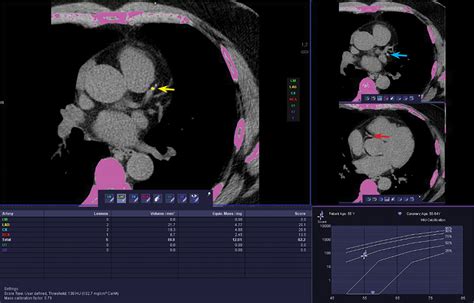

During a CAC scan, the patient lies on a table that slides into a CT scanner. The scanner takes multiple X-ray images of the heart from different angles. A computer then processes these images to create a detailed picture of the coronary arteries. The amount of calcium in the arteries is measured and given a score, known as the Agatston score.

Interpreting Coronary Artery Calcium Scores

The Agatston score is a numerical value that indicates the amount of calcium in the coronary arteries. The higher the score, the greater the risk of heart disease. Here is a general guide to interpreting CAC scores: